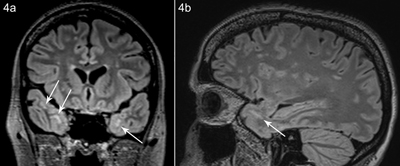

Patient B, 42 years old and a sister of patient A, presented to the neurologist for evaluation of possible myotonic dystrophy. Clinical examination revealed a slight myotic handshake, myopathic facial expression, and a bilateral Bell’s sign (suggestive of weakness of the orbicularis orbis muscles). Cardiac evaluation was normal. An MRI of the brain showed similar findings as patient A, although less pronounced (Figure 4).

Figure 4

Patient B, coronal (a) and sagittal (b) FLAIR image shows white matter hyperintensity subcortical anteromedial in the temporal lobe.